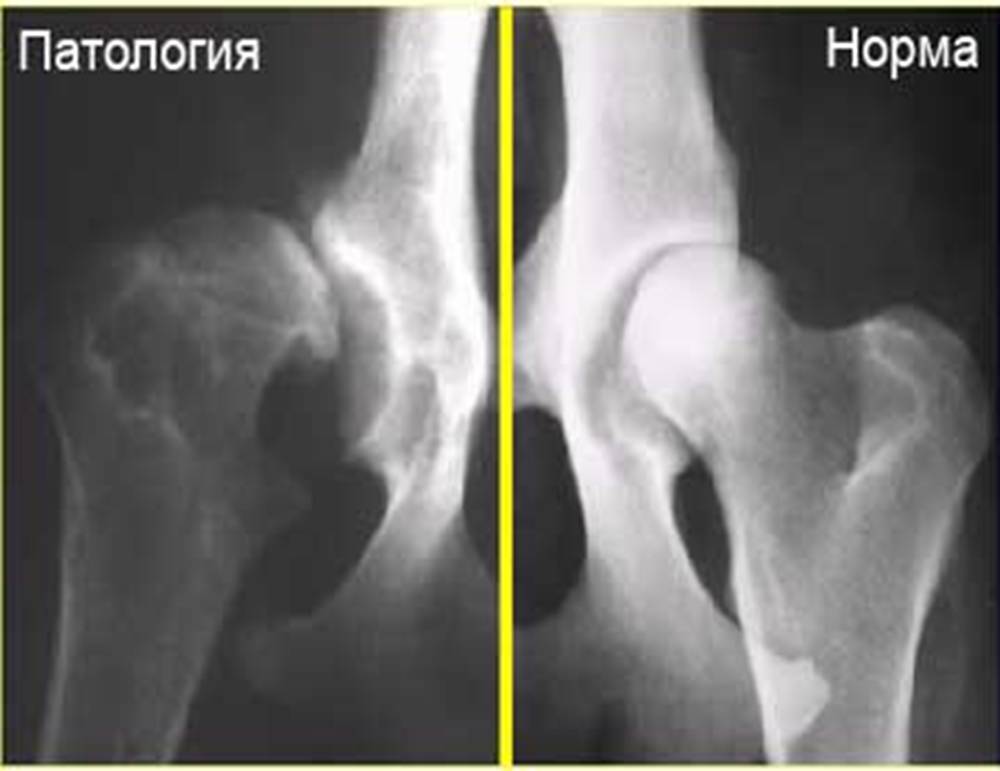

Дисплазия тазобедренного сустава (ТБС) - патология, при которой происходит вывих головки бедренной кости. Животное испытывает сильную боль, из-за которой ему сложно подниматься по лестницам и в целом ходить. Дисплазию можно определить по скованности движения. Различают умеренную и тяжёлую форму. Важна своевременная диагностика для выбора оптимальной терапии. Основной метод — рентгенография в положении стоя или лежа с разведёнными бедрами для оценки степени патологии.